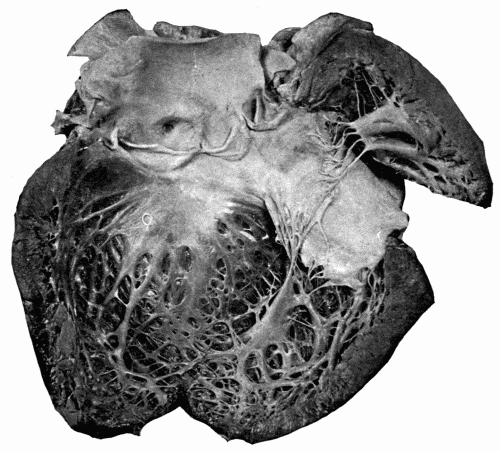

Fig. 12.—Aortic incompetence with hypertrophy and dilatation of left ventricle, the result of arteriosclerosis affecting the aortic valves. Note how the valves have been curled, thickened, and shortened, the edges of valves being a half inch below the upper points of attachment. The anterior coronary artery is shown, the lumen narrowed. (Reduced one-half.) Fig. 12.—Aortic incompetence with hypertrophy and dilatation of left ventricle, the result of arteriosclerosis affecting the aortic valves. Note how the valves have been curled, thickened, and shortened, the edges of valves being a half inch below the upper points of attachment. The anterior coronary artery is shown, the lumen narrowed. (Reduced one-half.)